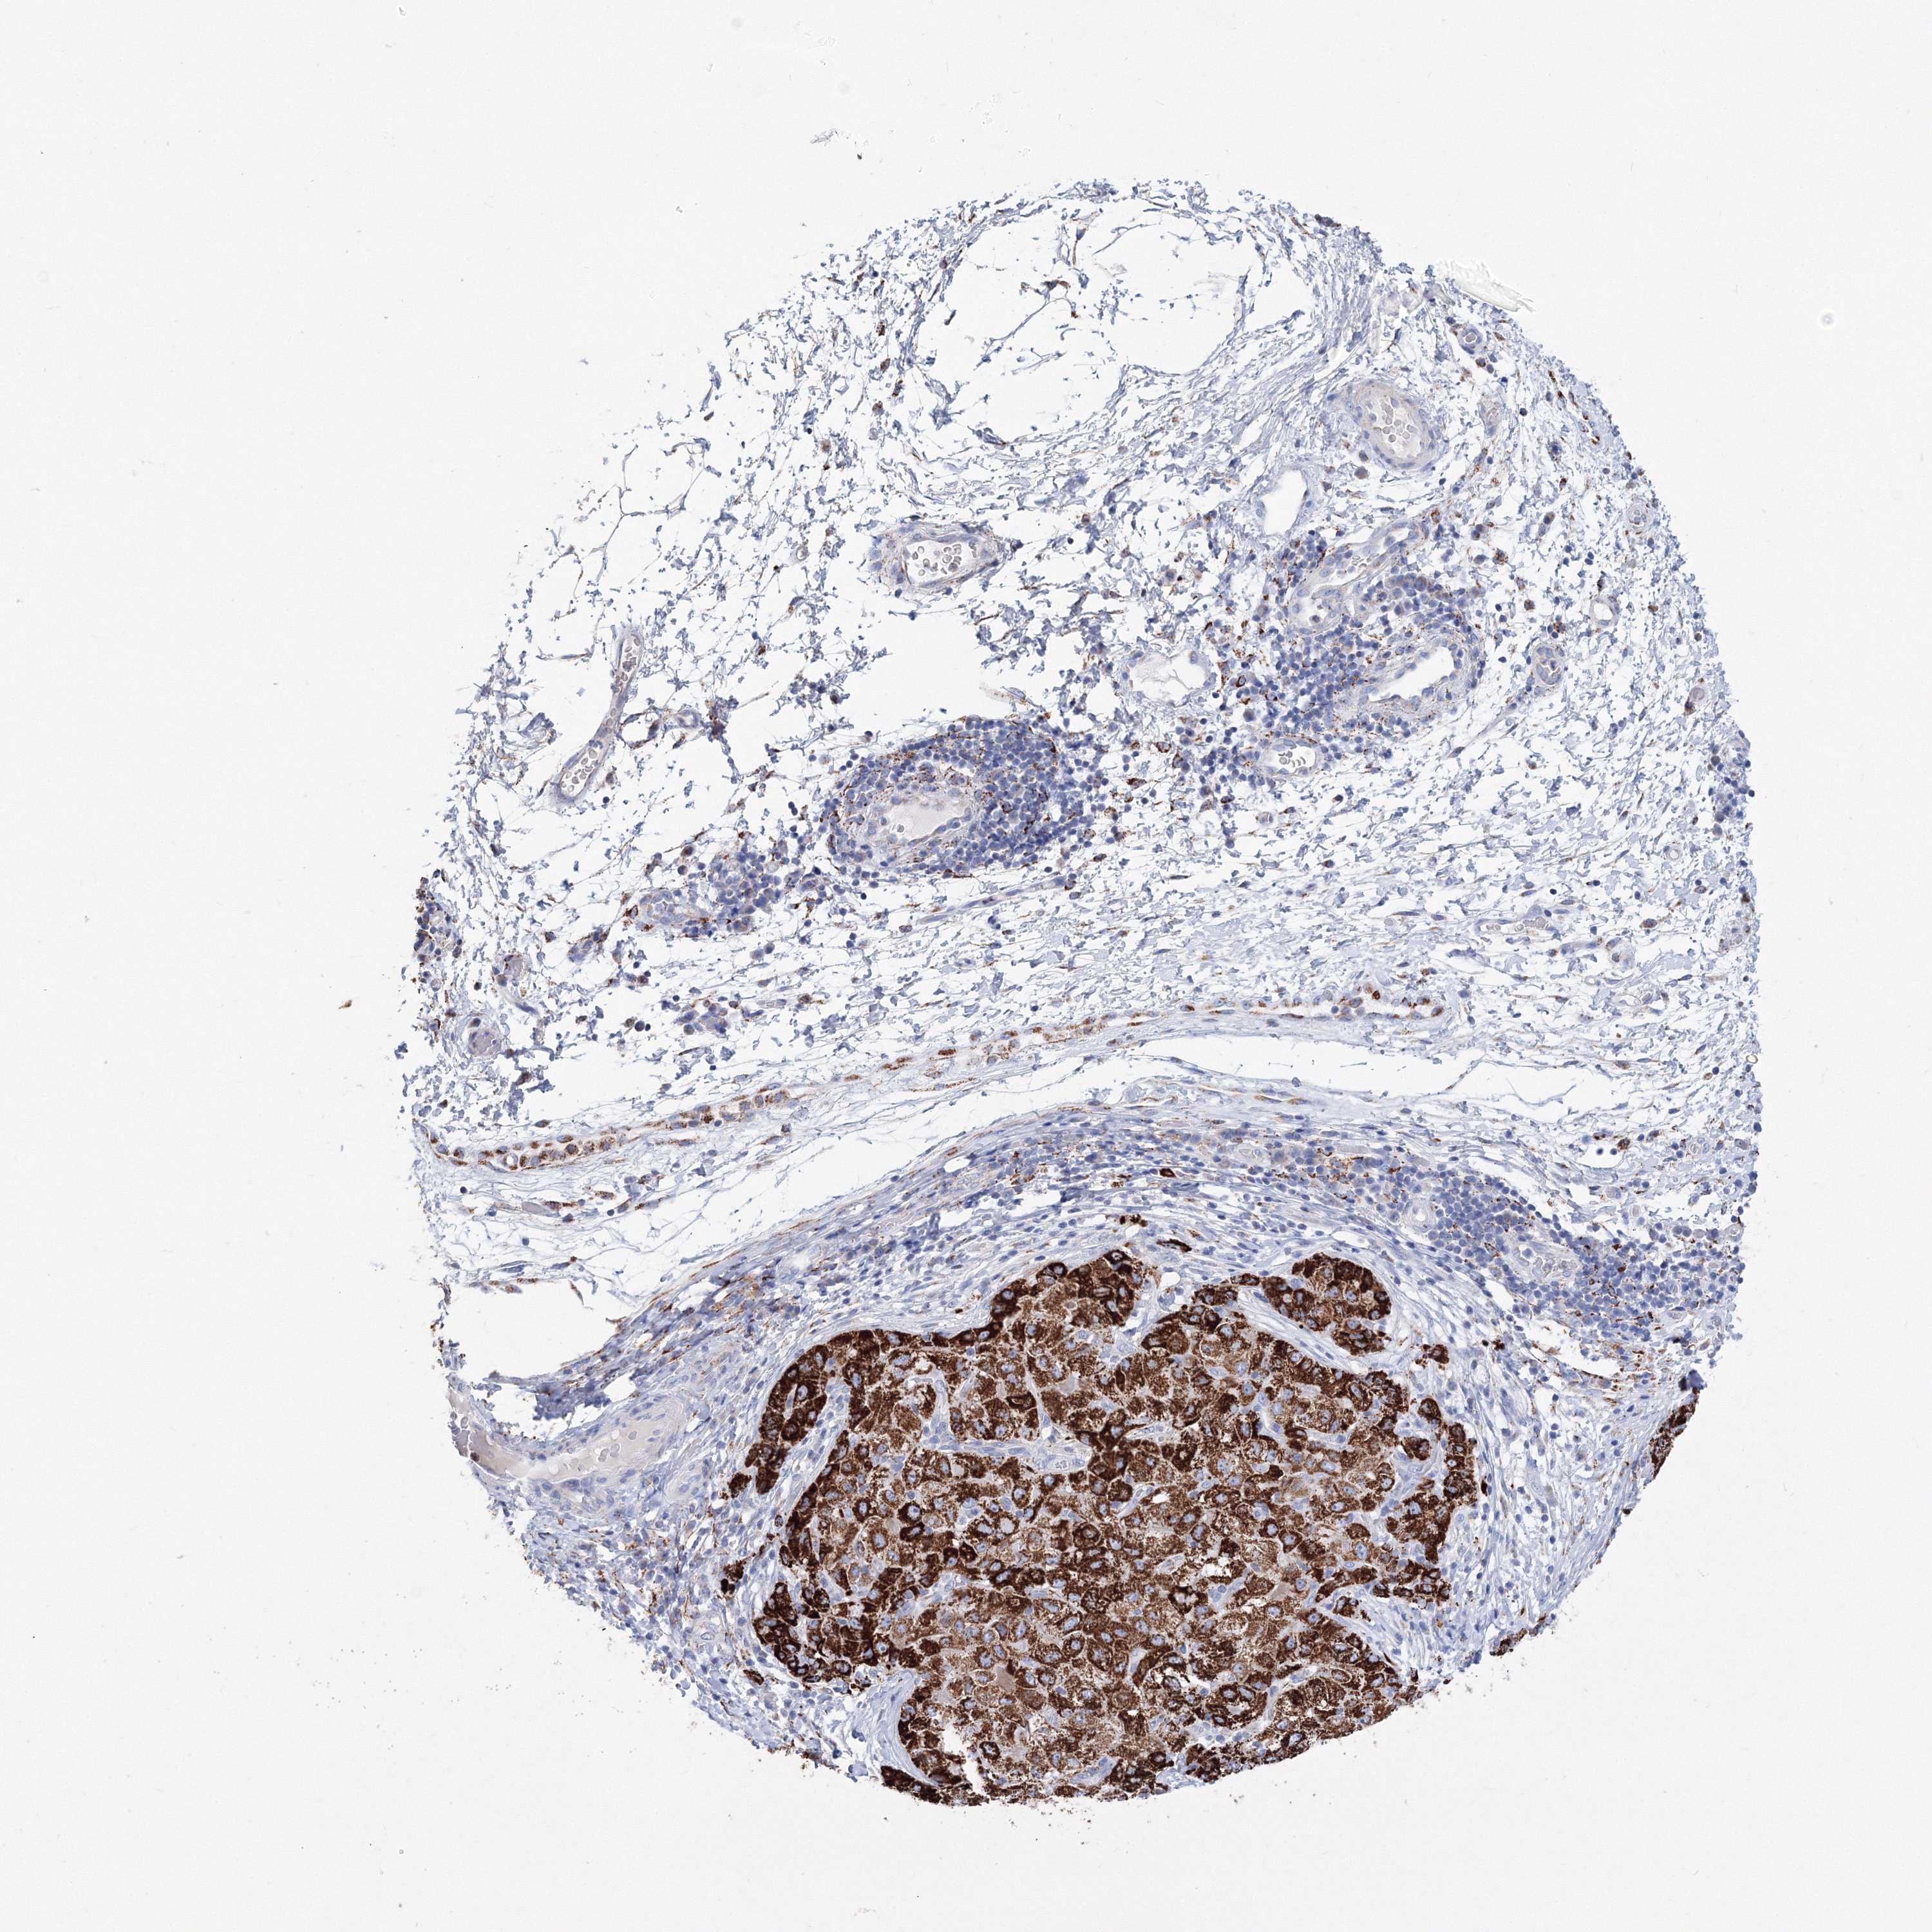

LIVER CANCER - Protein expressioni

A mouse-over function shows sample information and annotation data. Click on an image to view it in a full screen mode. Samples can be filtered based on level of antibody staining by selecting one or several of the following categories: high, medium, low and not detected. The assay and annotation is described here.

Note that samples used for immunohistochemistry by the Human Protein Atlas do not correspond to samples in the TCGA dataset.

Antibody stainingi

Antibody staining in the annotated cell types in the current human tissue is reported as not detected, low, medium, or high, based on conventional immunohistochemistry profiling in selected tissues. This score is based on the combination of the staining intensity and fraction of stained cells.

Each image is clickable and will lead to virtual microscopy that enables deeper exploration of all samples and also displays staining intensity scores, fraction scores and subcellular localization as well as patient and tissue information for each sample.

Antibody HPA036196

Staining

High

Medium

Low

Not detected

Intensity

Strong

Moderate

Weak

Negative

Quantity

>75%

75%-25%

<25%

None

Location

Nuclear

Cytoplasmic/membranous

Cytoplasmic/membranous,nuclear

Cholangiocarcinoma

Carcinoma, Hepatocellular, NOS